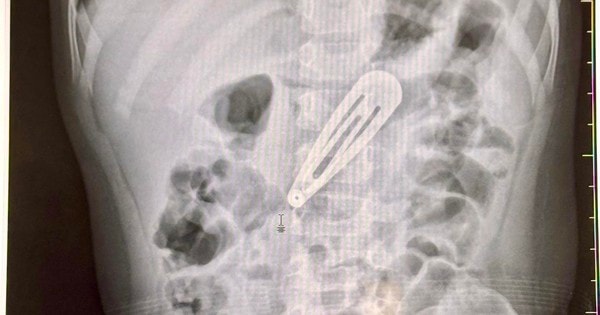

Bé gái 21 tháng tuổi nhập viện gấp với chiếc kẹp tóc trong dạ dày

Theo các bác sĩ, mặc dù dị vật không quá nhọn nhưng cạnh sắc và kích thước lớn dễ gây thủng rách trên đường di chuyển, đặc biệt khi xuống ruột non.